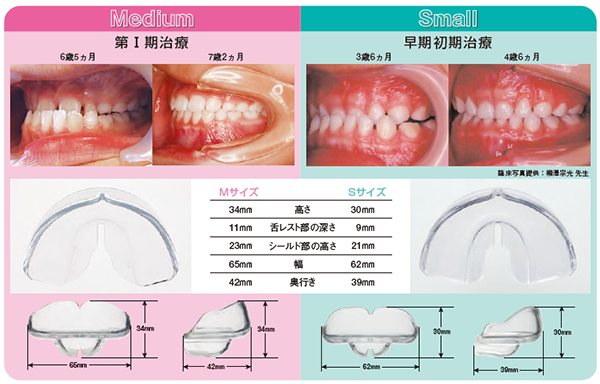

豪華 臨床 反対咬合/医歯薬出版株式会社 臨床医学